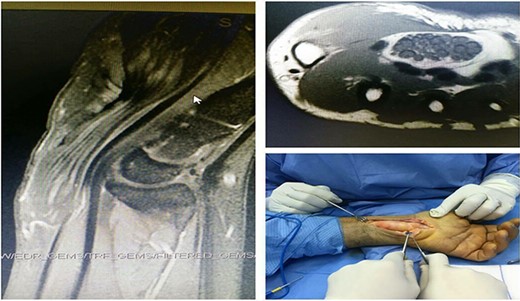

A 48-year-old man with a history of epilepsy successfully managed with sodium valproate appeared with swelling of the volar left wrist, discomfort in the radial three fingers, and paresthesia in the thenar region. The patient was tentatively diagnosed with a ganglion cyst pressing on the median nerve, which would explain the patient’s symptoms. The patient reported a 2*1 cm soft lump on the volar aspect of his wrist that extended to the palmar side of his hand. A thorough neurological evaluation showed normal distal pulses, capillary refill, and intact sensory and motor functioning of the radial, ulnar, and median nerves. Tinel and Phalen’s testing showed no signs of thenar atrophy. Ultrasound imaging showed a hyperechogenic lesion measuring about 2*0.64 cm adjacent to the left wrist with no vascular activity. The skin had thickened at the bottom of the left thumb into a roughly 0.51*0.84 cm lesion. The magnetic resonance imaging (MRI) scans showed an abnormally expanded median nerve with a ‘coaxial cable’ or ‘spaghetti-like’ appearance due to its enlarged cylindrical fascicles with a central intermediated focus in T1 and relatively high signal intensity in T2, surrounded by fat (Fig. 1). Histopathological confirmation of the MRI diagnosis of a tumour in the nerve sheath or a fibrolipomatous hamartoma of the median nerve was deemed necessary. Surgery to relieve pressure on the median nerve, including removing the protective sheath and opening the carpal tunnel, was scheduled for a day. During the operation, the incision was prolonged proximally to include the mid-forearm and the distal palmar crease, demonstrating that the lesion’s borders extended into the median nerve. The lesion was safely isolated, whereas the nerve sheath was removed (Fig. 2). The wound closure was difficult, but it was accomplished. The patient was substantially less symptomatic after surgery, and he was monitored for three years. At the time of the most recent checkup, the patient had a full range of motion in his wrists and fingers, and his sensorium was unimpaired (Fig. 3). According to nerve conduction testing, significant axonal damage in the median nerve at the wrist and fingers indicated severe left carpal tunnel syndrome.

Ultrasound imaging showed a hyperechogenic lesion adjacent to the left wrist; MRI scans showed an abnormally expanded median nerve with a coaxial cable or spaghetti-like appearance.